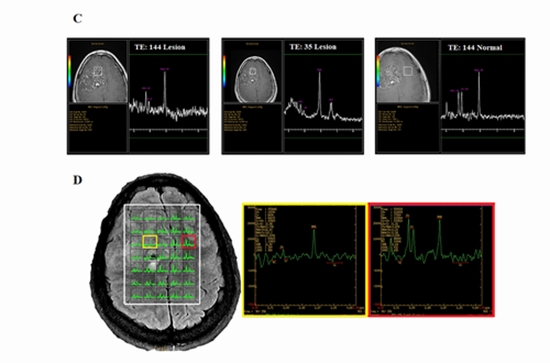

Introduction: Intracranial chondroma and chondrosarcoma are very rare tumors that mainly originate from the base of the skull. Advanced neuroimaging studies, including magnetic resonance spectroscopy (MRS), play a pivotal role in both tumor diagnosis and presurgical planning. Case Presentation: We present two cases of intracranial cartilaginous tumors, including a chondroma and a chondrosarcoma, both of which presented with severe headaches. Due to inconclusive conventional MRI and MRS results, they were both primarily diagnosed as intra-axial brain tumors. However, pathological reports later confirmed the diagnosis of a chondroma and a chondrosarcoma. Conclusion: Based on the present findings, the use of advanced neuroimaging techniques, such as MRS, may improve diagnostic accuracy. We believe that MRS can play a significant role in the surgical planning of similar cases. Also, reporting rare cases worldwide can contribute to the improvement of radiographic diagnosis.